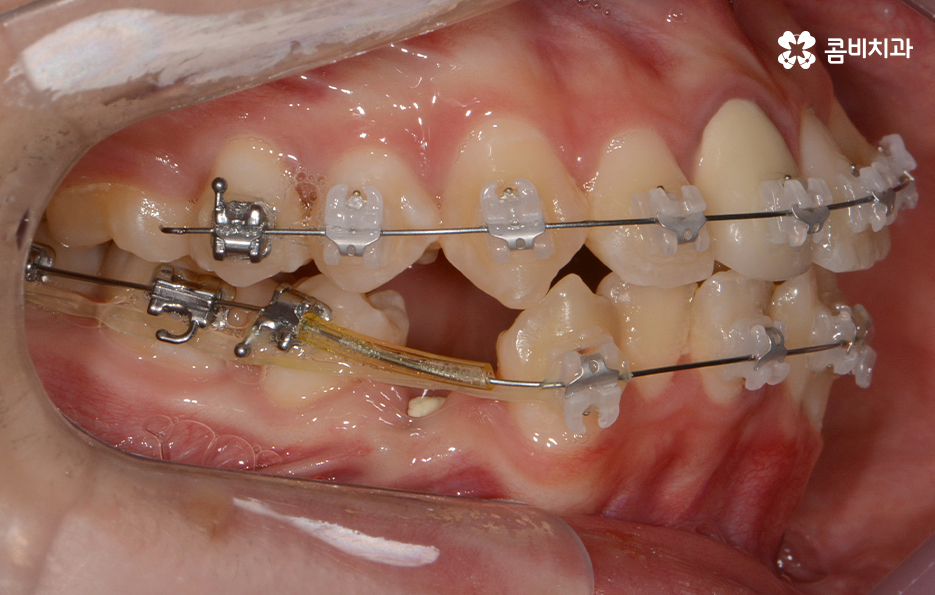

참고로 이번 포스팅에 소개해드린 환자분의 경우

검진부터 발치, 클리피씨 교정을 통해 교정이

마무리 되기 까지 약 2년 정도가 걸렸으며

치료 기간은 개인에 따라 상이하며 정확한 검진 후에

치료 계획에 따라 달라질 수 있어요.

위 환자분의 케이스는 아랫니에 치아 2개를 발치하여

치아의 이동 공간을 확보하였고 발치교정이 진행될 때는

윗니와 아랫니 각각 2개씩 발치를 하는 경우가 많지만

위 사례는 치열, 교합 등을 고려할 때 아랫니 2개만

발치가 진행되었던 경우라고 볼 수 있어요.